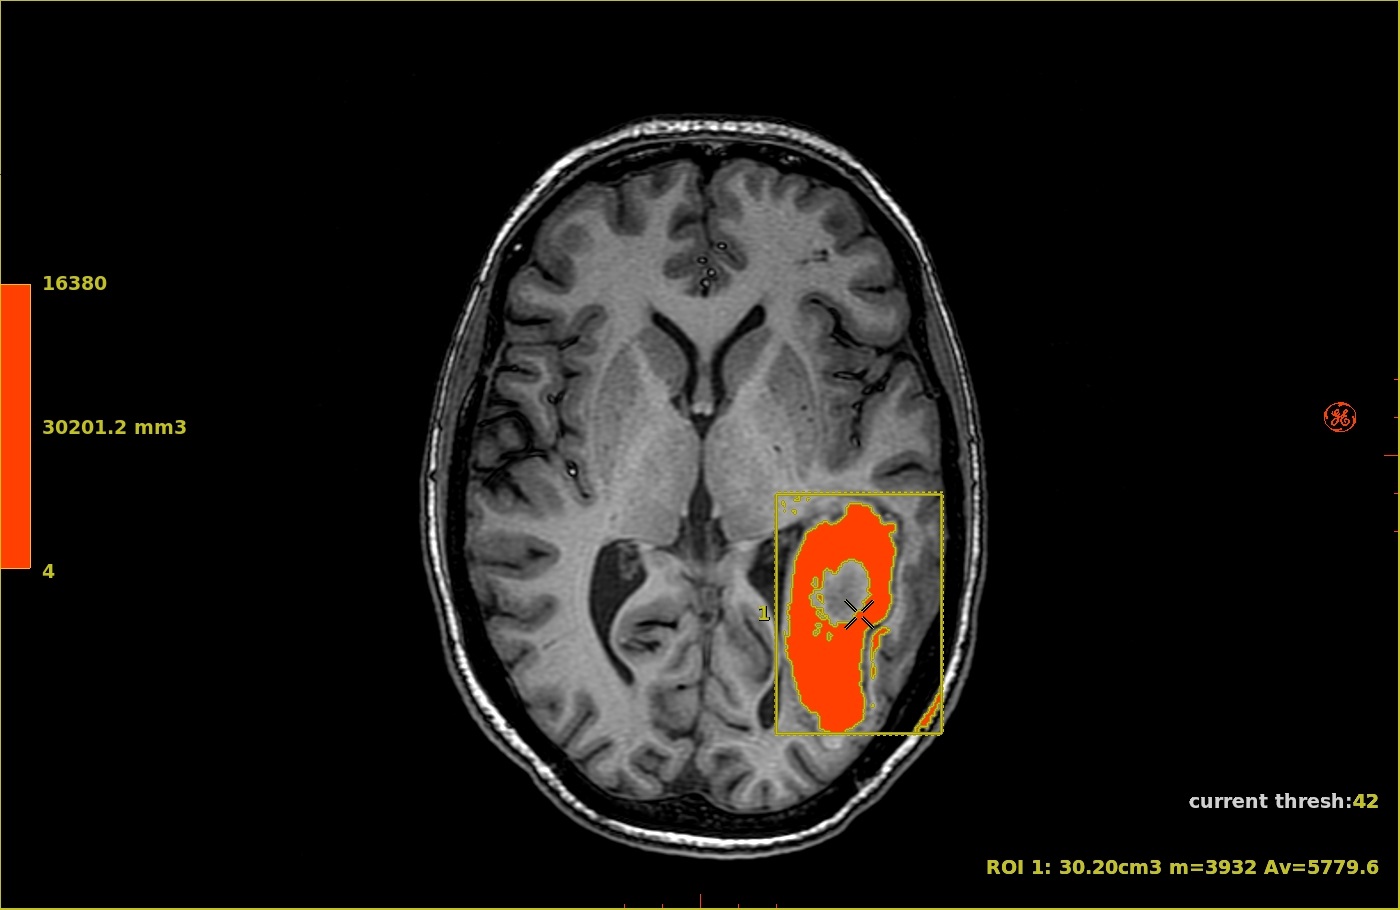

Figure 2. Colors match the corresponding color ramp